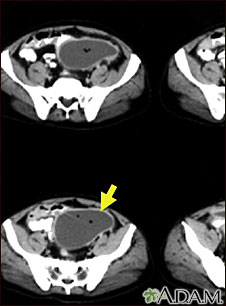

CT scan of the pelvis showing a large intra-abdominal mass.